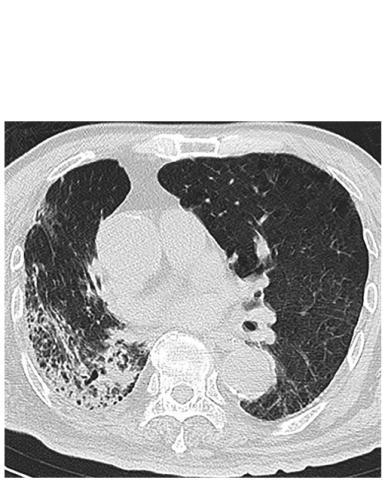

Une ligne pleurale très épaissie (Visuel ci-dessous) caractéristique des cas plus sévères et qui persiste sur une longue durée après l'apparition des symptômes dans les cas critiques, ces nouvelles observations à l’échographie pulmonaire, documentées dans l’American Journal of Roentgenology (AJR) vont permettre aux spécialistes de mieux caractériser les cas à risque élevé. Ces données viennent confirmer le rôle clé de l’imagerie dans le diagnostic de la maladie et de son risque de complications.

Ces chercheurs de l'hôpital de Beijing montrent que l'échographie pulmonaire est très sensible pour détecter les anomalies chez les patients COVID-19, avec en particulier une ligne pleurale épaissie et une consolidation pulmonaire fréquemment observées dans les cas plus critiques. De plus, les chercheurs suggèrent que l’imagerie pulmonaire peut également refléter la durée de l'infection.

Les 28 patients de l’étude, 14 hommes et 14 femmes, âgés de 21 à 92 ans ont obtenu des résultats positifs à la fois à l'échographie pulmonaire et au scanner thoracique. A l’échographie,

- des lignes B sont présentes chez 100% des patients,

- une consolidation pulmonaire chez 68% des patients,

- un épaissement de la ligne pleurale chez 61% des patients,

- un seul patient a présenté un petit épanchement pleural.

- L’épaississement de la ligne pleurale est plus fréquemment observé chez les patients longtemps après l'apparition initiale des symptômes, c’est-à-dire chez des patients dont la maladie dure longtemps ;

- les consolidations pulmonaires ou zones hypoéchogènes "ressemblant à des tissus", reflétant un débit d'air très réduit et une quantité accrue d'exsudat cellulaire inflammatoire sont plus fréquemment rencontrées dans les cas graves et critiques ;